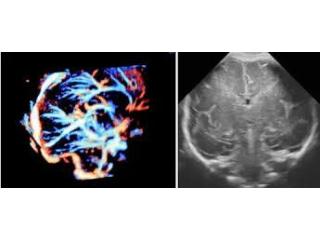

Elevate your prenatal care with Fetal India's advanced Fetal Neurosonography services. Unmatched in accuracy and resolution, our imaging techniques offer a comprehensive view of your baby's developing brain, aiding in the early detection of any neurological issues. Rest assured, our team of experienced professionals will provide personalized care and reliable results to support you throughout your pregnancy journey.